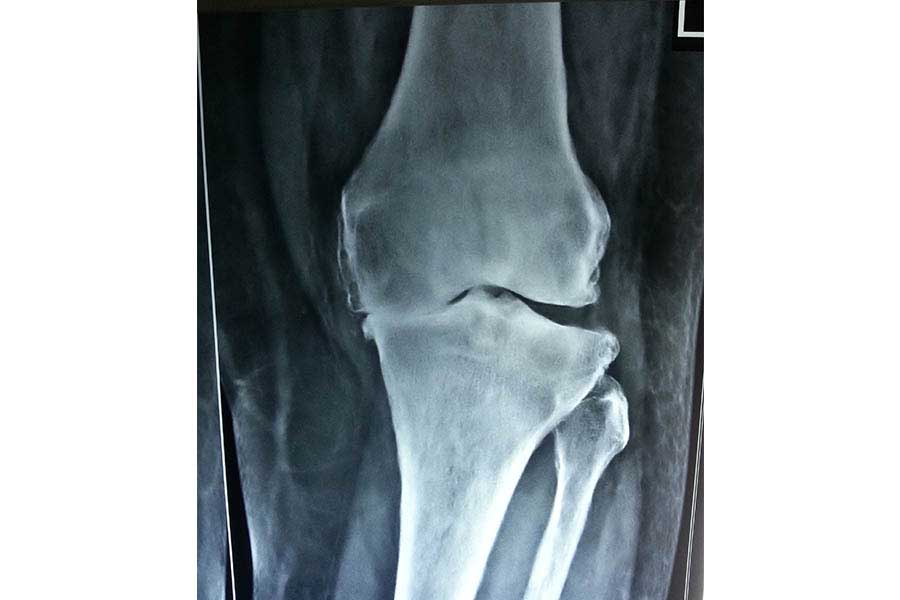

Total Knee Replacement

Complicated Joint Replacement

Case 1